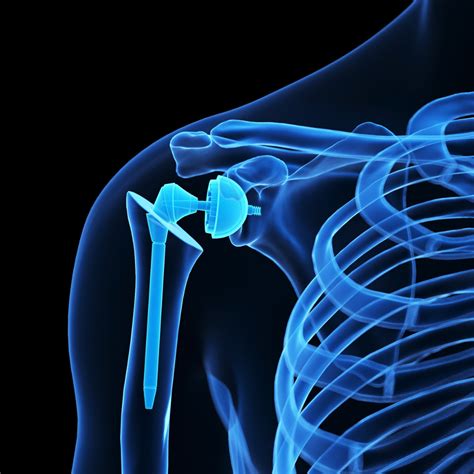

• Anatomic Total Shoulder Replacement: This is used when the rotator cuff tendons are healthy. The surgeon replaces the ball and socket with components that mimic the original anatomy.

• Reverse Total Shoulder Replacement: Designed for patients with severe rotator cuff tears or arthritis where the tendons are irreparable. In this case, the position of the ball and socket is reversed, allowing the deltoid muscle to take over the movement of the arm.

• Hemiarthroplasty: Only the humeral head (the ball) is replaced, while the original socket remains untouched. This is typically performed for specific fracture cases.